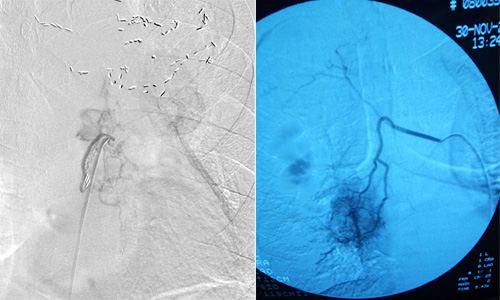

医院呼吸内一科介入团队根据病症情况,成功为该患者实施经支气管动脉灌注化疗栓塞术。手术精准、微创、无痛,全过程仅需局部麻醉,患者术后一天即可下床行走。

中晚期肺癌难以采取手术切除,尽管化疗药物和放疗技术的不断更新,传统的放、化疗的有效率还是非常低。支气管动脉灌注化疗栓塞术是在患者腹股沟区用穿刺针作直径几毫米的微小通道,然后把化疗药物通过导管直接输送到肿瘤,进行局部精准化疗,浓度可以达到静脉化疗药物浓度的400倍以上,对肿瘤的杀伤力很强,同时其全身反应要小于静脉给药。给药完成后,也可栓塞肿瘤血管,阻断肿瘤的血供营养,从而“饿死”肿瘤,达到“治、控”结合的治疗目的。